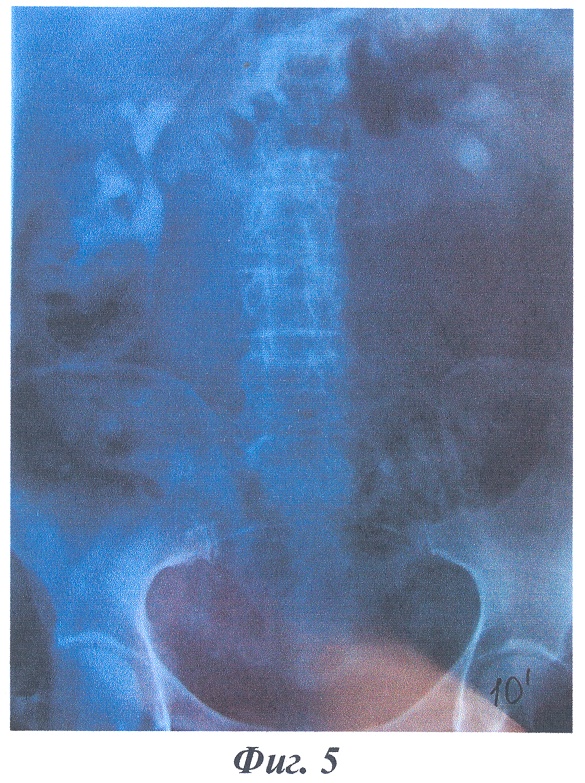

На фиг.4-6 изображены рентгенограммы клинического примера формирования накопительного мочевого резервуара предлагаемым способом.

В качестве примера приводится выписка из истории болезни больной Ж., 51 года, И.Б. №1111, которой по поводу постлучевой облитерации мочевого пузыря и уретры после лечения рака шейки матки T1N0M0 (фиг.4 – экскреторная урограмма до операции) 12.04.2004 г. была произведена операция (№169) с формированием “сухой” накопительной уростомы по предложенному способу. Послеоперационное течение гладкое, больная выписана в удовлетворительном состоянии на 29 сутки после операции.

Заключительный диагноз: постлучевая облитерация мочевого пузыря и уретры. Состояние после лечения рака шейки матки T1N0M0. Больная осмотрена через 2 года, данных за рецидив и метастазы не выявлено, при экскреторной урографии отмечается удовлетворительная функция почек, расширения чашечно-лоханочных систем и мочеточников нет (фиг.5, 6).